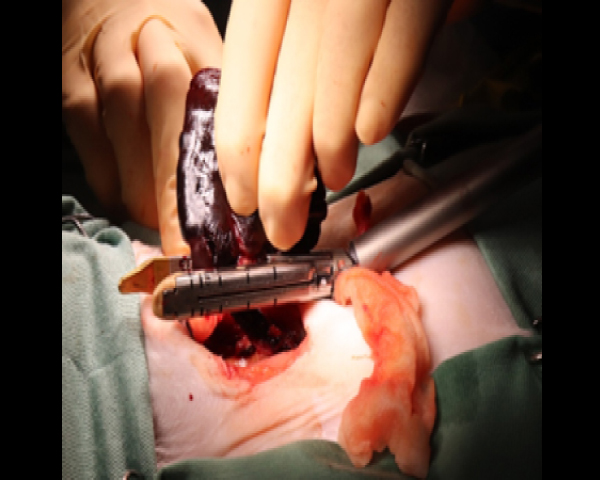

エンドGIAを用いた肺葉切除